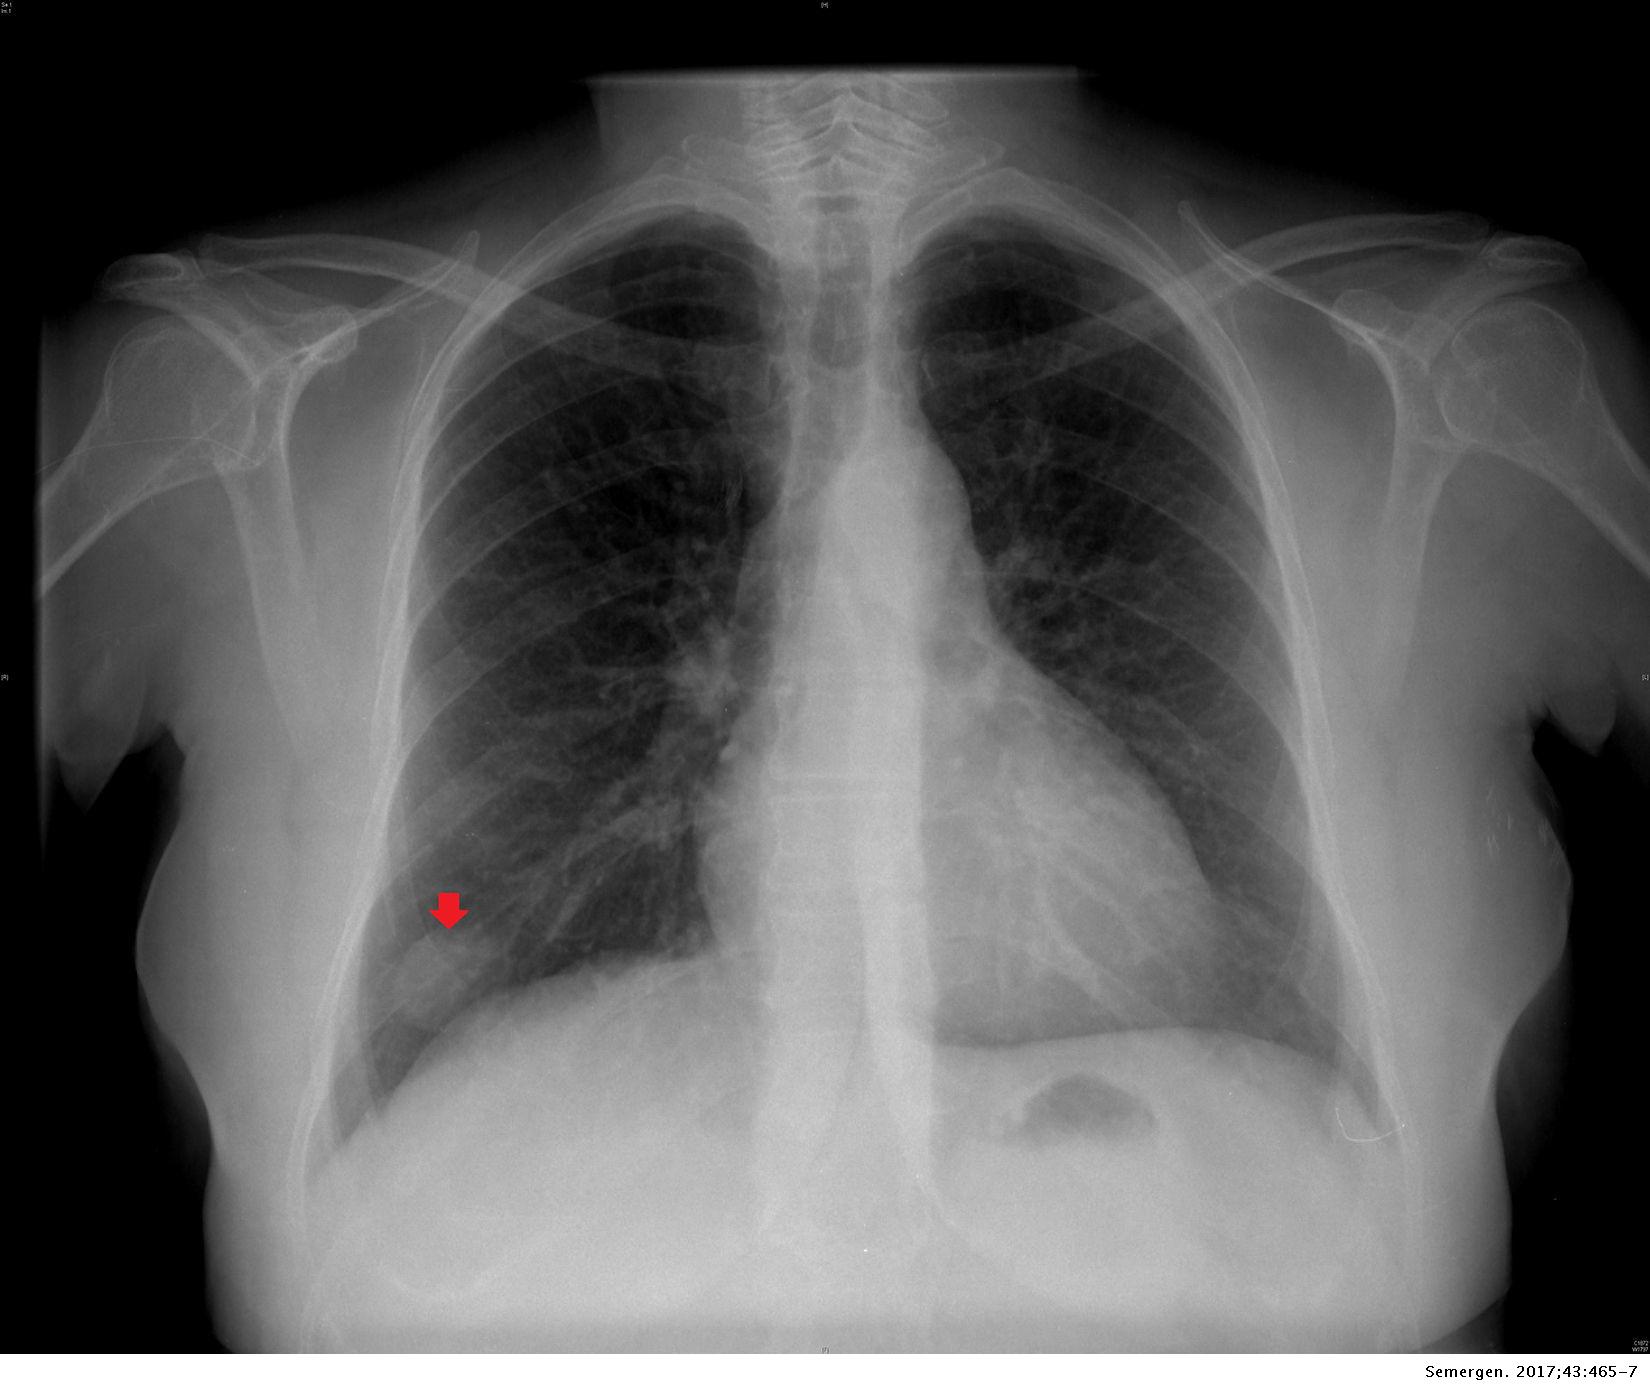

Hamartoma pulmonar como presentación de un nódulo pulmonar solitario Medicina de Familia. SEMERGEN

Nódulos pulmonares y compromiso pulmonar intersticial. A) Radiografía… Download Scientific